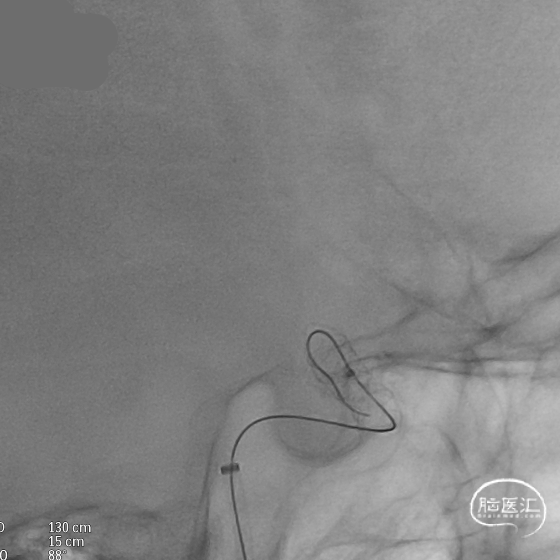

术后造影:支架充分覆盖动脉瘤瘤颈,贴壁良好,瘤体内可见造影剂滞留。

术后支架显影:定位精准,未覆盖颞前动脉及大脑前动脉。